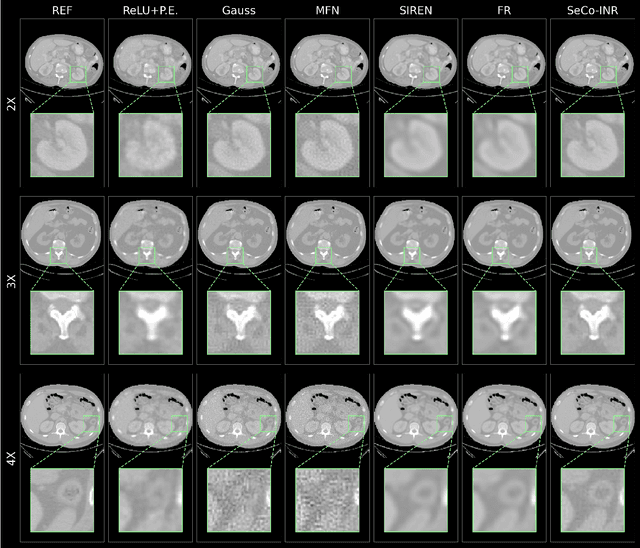

Abstract:Implicit Neural Representations (INRs) have recently advanced the field of deep learning due to their ability to learn continuous representations of signals without the need for large training datasets. Although INR methods have been studied for medical image super-resolution, their adaptability to localized priors in medical images has not been extensively explored. Medical images contain rich anatomical divisions that could provide valuable local prior information to enhance the accuracy and robustness of INRs. In this work, we propose a novel framework, referred to as the Semantically Conditioned INR (SeCo-INR), that conditions an INR using local priors from a medical image, enabling accurate model fitting and interpolation capabilities to achieve super-resolution. Our framework learns a continuous representation of the semantic segmentation features of a medical image and utilizes it to derive the optimal INR for each semantic region of the image. We tested our framework using several medical imaging modalities and achieved higher quantitative scores and more realistic super-resolution outputs compared to state-of-the-art methods.